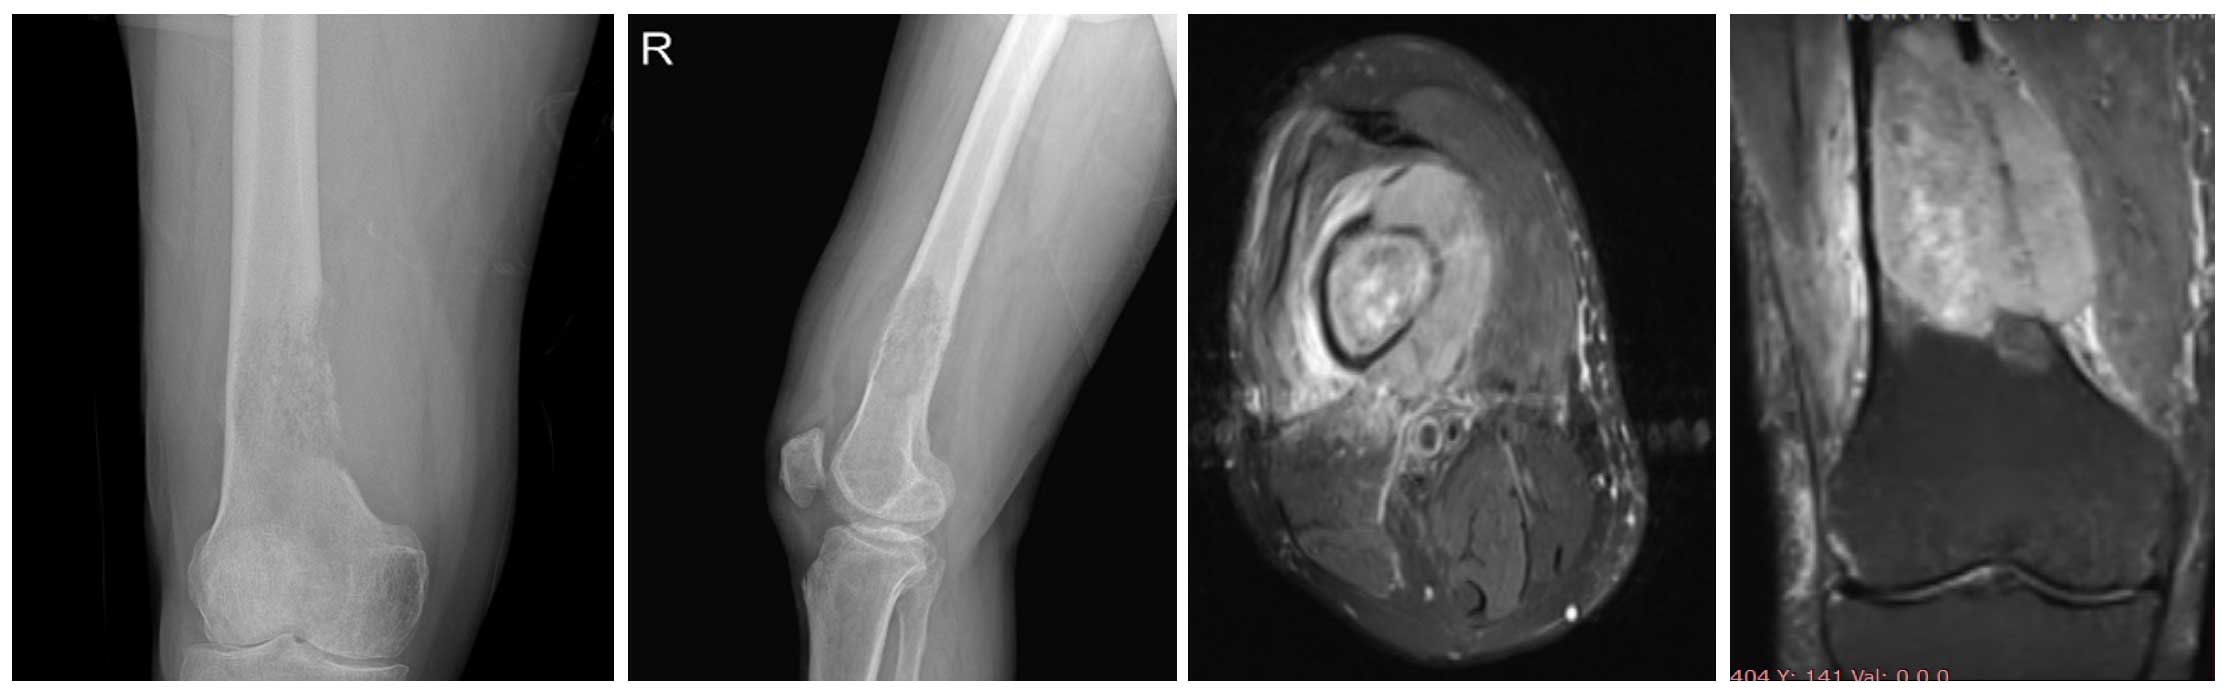

Ameliyat Öncesi: Röntgende sağ uyluk kemiği alt uç iç kısımda yeniklik ve harabiyet, MR’da eşlik eden tümör kitlesi ve çevreleyen ödem görülmekte.